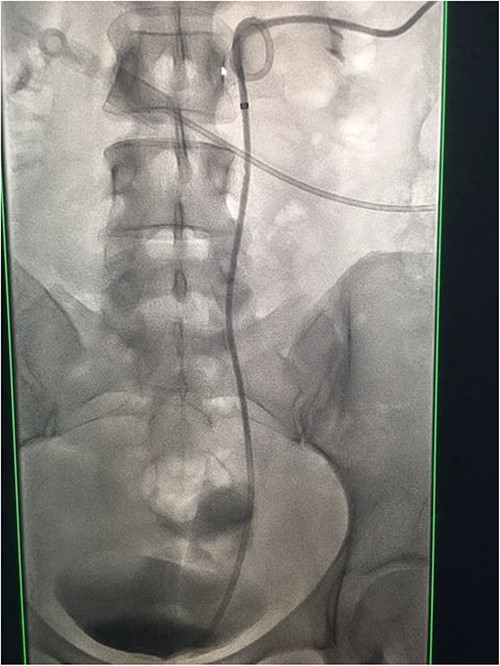

Under conscious sedation, using the previously inserted right percutaneous nephrostomy, antegrade access was achieved into the intrarenal collecting system and then into the proximal ureter. An 8 Fr × 11-cm access sheath was introduced. A guidewire was advanced antegradely through the site of ureteric transection and coiled in a position adjacent to the position of the guidewire that had been inserted retrogradely. A Gooseneck snare catheter was then passed over the guidewire and the snare was inserted (Figs 4 and 5). Under fluoroscopic guidance, the retrograde wire was retrieved and brought externally via the nephrostomy site, achieving through-and-through wire access (Figs 6 and 7).

Fluoroscopic images showing the retrograde wire successfully retrieved and brought externally via the nephrostomy site, achieving through-and-through wire access.

A catheter-guidewire exchange was performed to upsize the guidewire to a 0.035-inch stiff guidewire. An 8-Fr, 26-cm nephroureteric stent was inserted over the guidewire in an antegrade manner (Fig. 8). The stent was left to free external drainage. The patient was transferred back to the ward and discharged home the following day. Trial without bladder catheter was successfully undertaken 1 week post-procedure.

Fluoroscopic images demonstrating the successfully re-connected right ureter with a nephroureteric stent in situ.